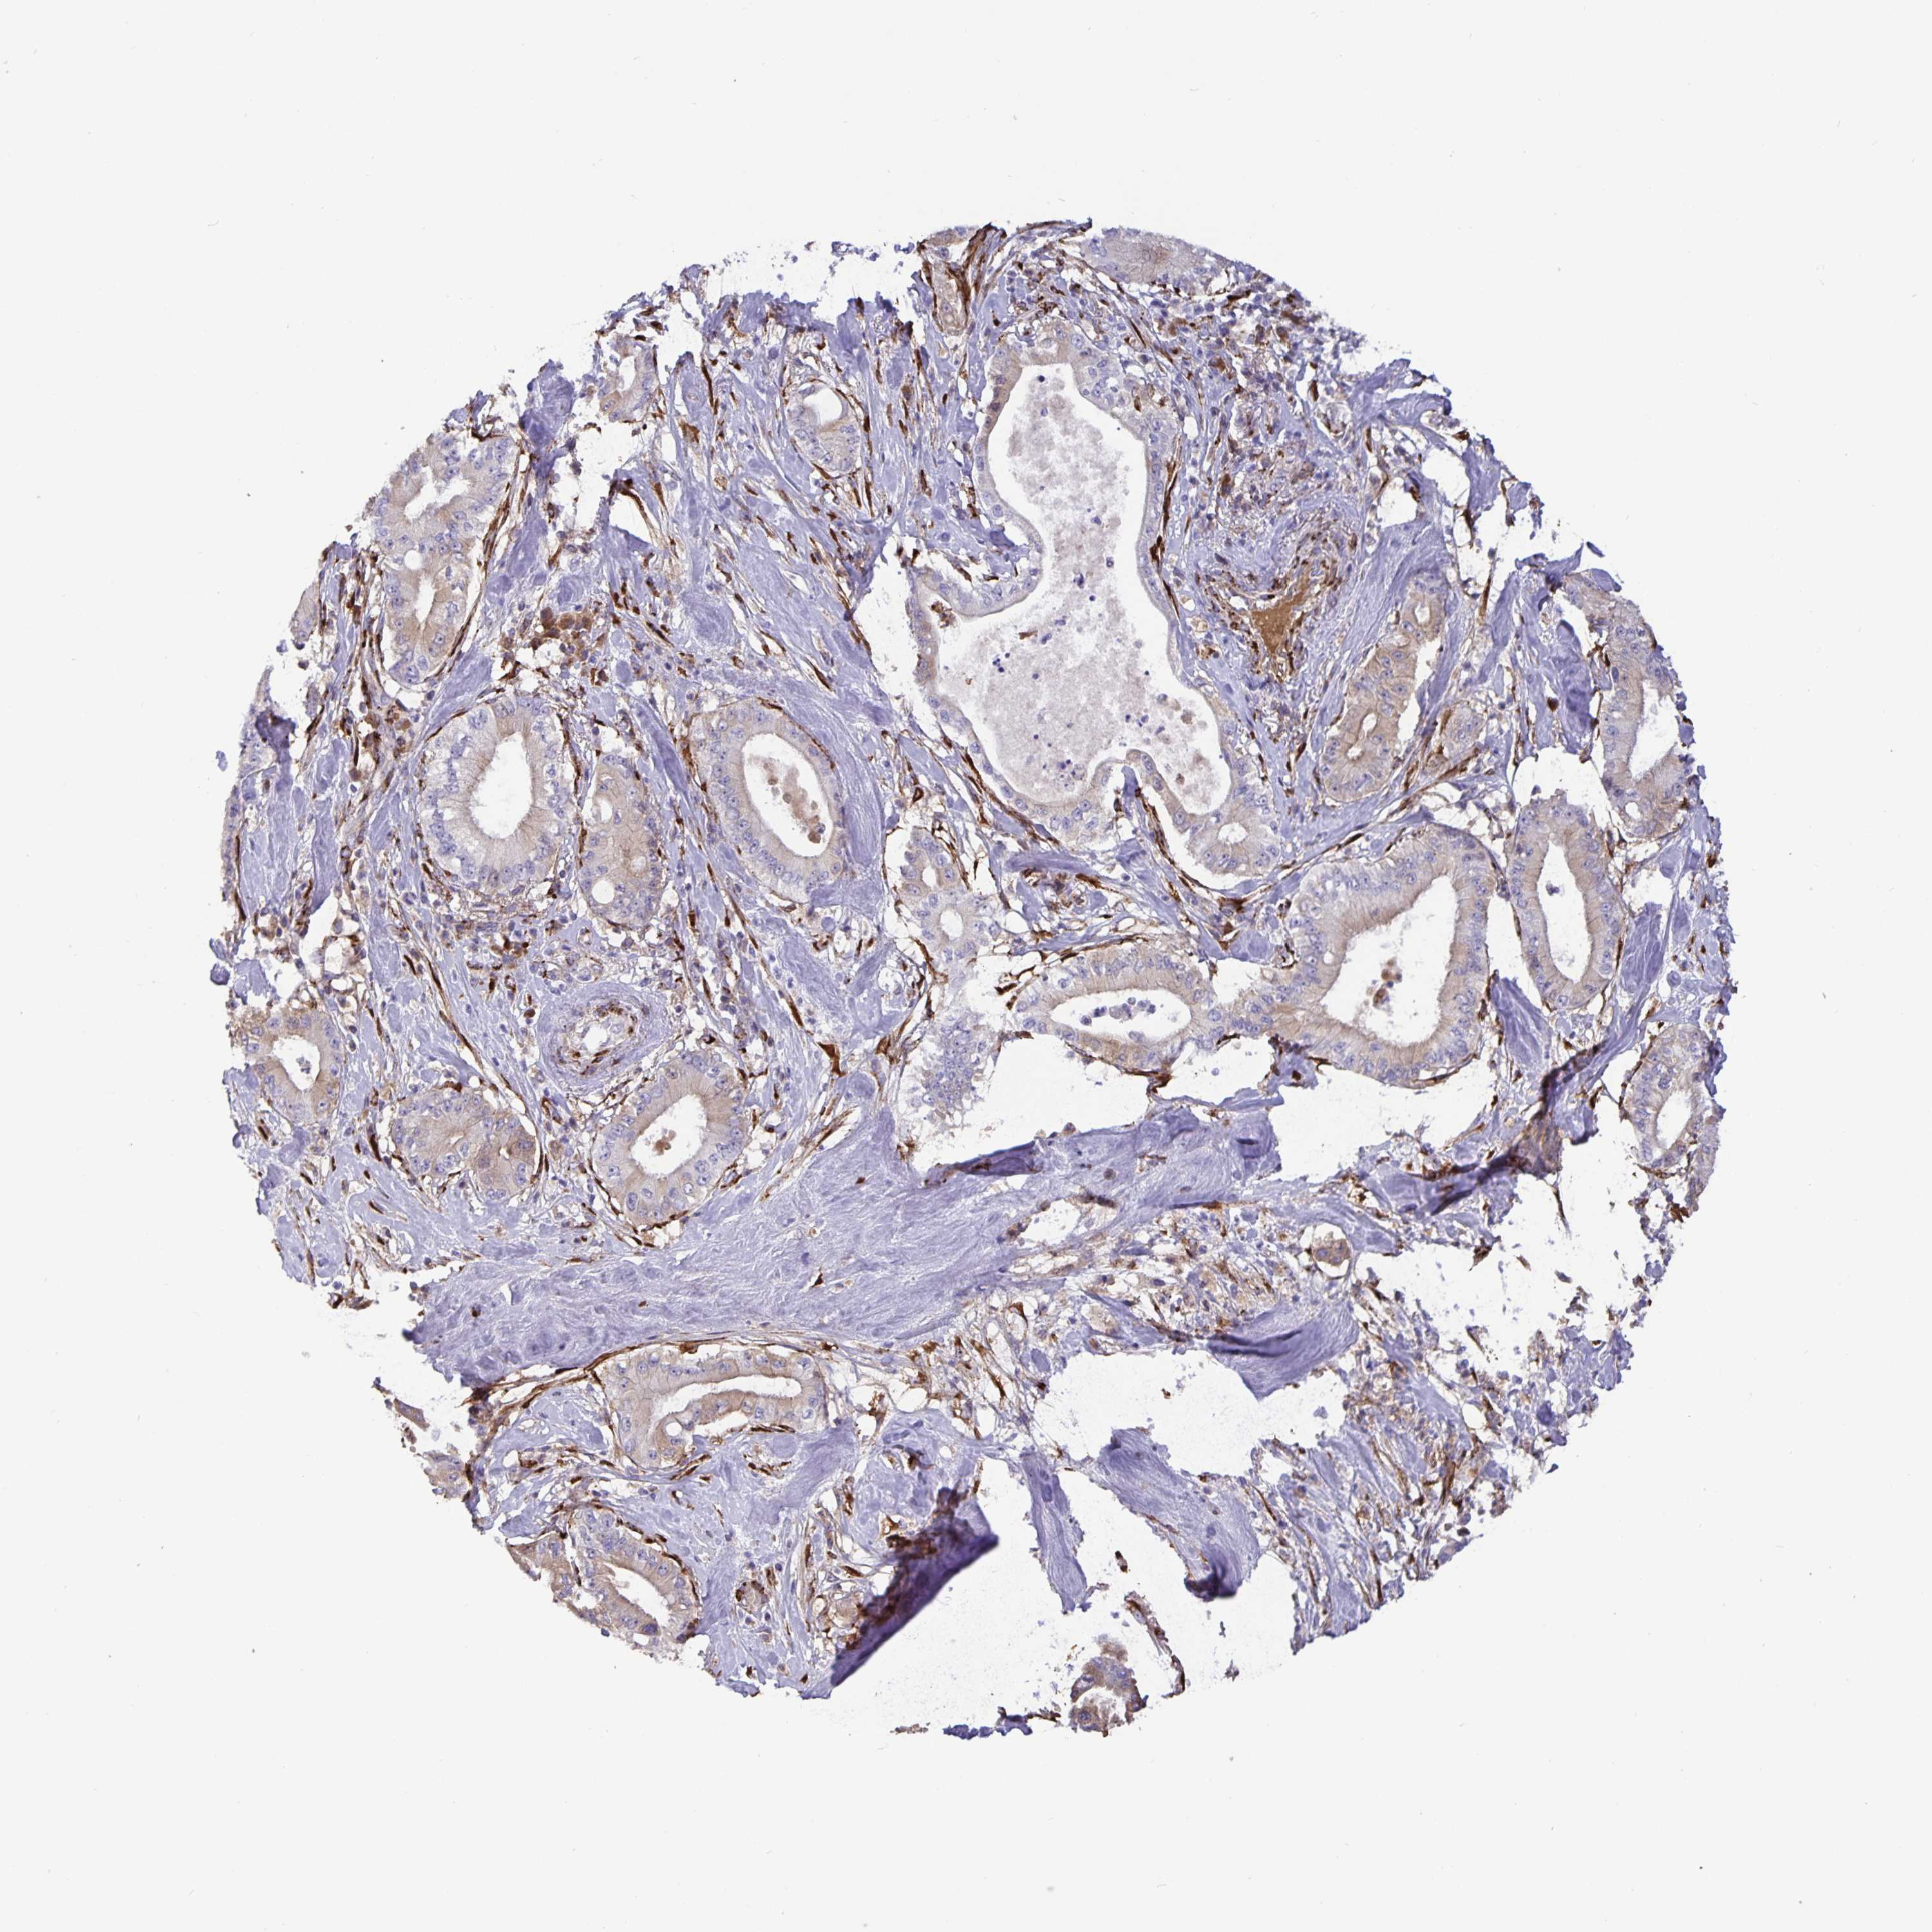

PANCREATIC CANCER - Protein expressioni

A mouse-over function shows sample information and annotation data. Click on an image to view it in a full screen mode. Samples can be filtered based on level of antibody staining by selecting one or several of the following categories: high, medium, low and not detected. The assay and annotation is described here.

Note that samples used for immunohistochemistry by the Human Protein Atlas do not correspond to samples in the TCGA dataset.

Antibody stainingi

Antibody staining in the annotated cell types in the current human tissue is reported as not detected, low, medium, or high, based on conventional immunohistochemistry profiling in selected tissues. This score is based on the combination of the staining intensity and fraction of stained cells.

Each image is clickable and will lead to virtual microscopy that enables deeper exploration of all samples and also displays staining intensity scores, fraction scores and subcellular localization as well as patient and tissue information for each sample.

Antibody HPA062808

Staining

High

Medium

Low

Not detected

Intensity

Strong

Moderate

Weak

Negative

Quantity

>75%

75%-25%

<25%

None

Location

Nuclear

Cytoplasmic/membranous

Cytoplasmic/membranous,nuclear

Adenocarcinoma, NOS